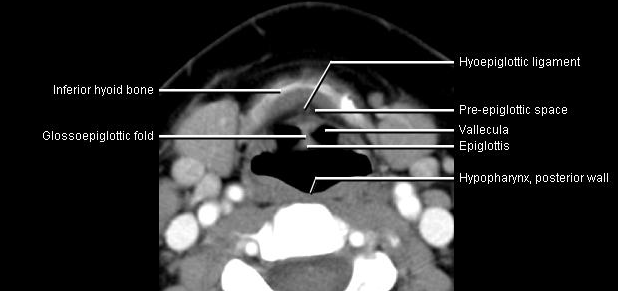

Phonation and dysphagia involve multiple coordinated structures in the larynx and pharynx. Radiation induced dysphagis appears to be related to dose to the phyaryngeal constrictor muscles and specific regions of the supraglottic and glottin larynyx.

Speech is impacted by doses to the epiglottis, base of tongue, aryepiglottic folds, false vocal cords upper esophageal sphincter and cricoid cartilage.

The mean laryngeal volume receiving > 50 Gy was a predictor of laryngeal edema. Vocal functions are usually well preserved with doses of 60 - 66 Gy. Dornfeld found a strong correlation between speech quality and dose to the ariepiglottic folds, pre-epiglottic space, false vocal cords and lateral pharyngeal walls at the level of the false vocal cords. A steep decrease in dose function was noted when doses exceeded 66 Gy.